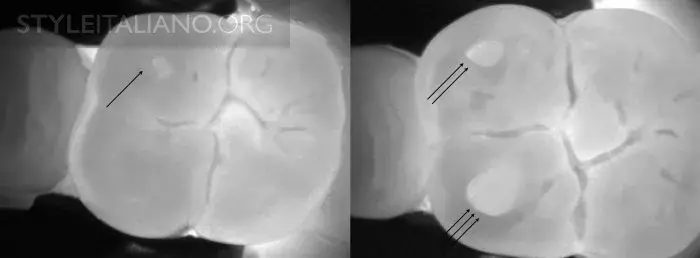

Рис. 8 – Фиссура - одна из анатомически сложнейших областей зуба. Мы можем получить представление о происходящих в ней процессах - фиссурном кариесе.

Рис. 17 – Рентген слева, просвечивание справа.

Рис. 19 – Рентген и просвечивание.